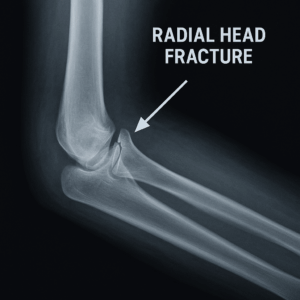

A radial head fracture occurs when the radial head (the top of the radius bone on the thumb side of your forearm) breaks. This bone helps stabilize the elbow and allows forearm rotation, such as turning a doorknob or key.

X-rays to confirm fracture location and displacement

CT scan (if needed) for complex fractures or surgical planning